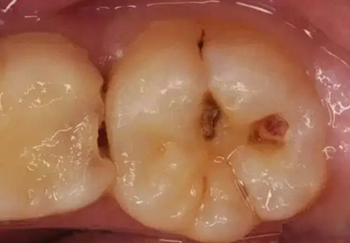

第二步:中齲

當(dāng)您吃糖時(shí),感覺(jué)酸疼,您說(shuō):“沒(méi)關(guān)系,不是很疼。”

牙醫(yī)卻說(shuō):“這時(shí)病變已經(jīng)破壞到牙本質(zhì)淺層了,牙齒已經(jīng)有齲洞形成,對(duì)酸甜食物敏感,需要做充填治療。”

第三步:深齲

當(dāng)您進(jìn)食時(shí),沒(méi)法咬食物,您說(shuō):“還好,可以用另外一邊牙齒咬。”

牙醫(yī)告誡說(shuō):“病變已經(jīng)破壞到了牙本質(zhì)深層,牙齒有較深的齲洞,溫度刺激,化學(xué)刺激以及食物進(jìn)入齲洞時(shí)均引起疼痛,此時(shí),及時(shí)做充填治療的話還來(lái)得及保住牙髓。”